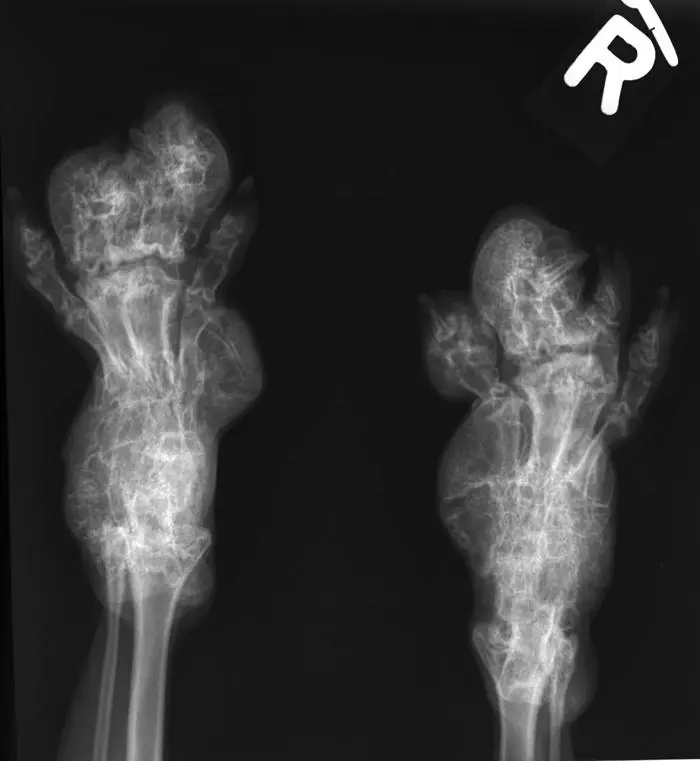

Röntgen einer deformierten Faltohrkatze, die eingeschläfert werden musste

Röntgen einer deformierten Faltohrkatze, die eingeschläfert werden musste © Tierschutzombudsstelle Wien/KK

Die Katzen werden durch Gelenksschwellungen, verdickte und missgestaltete Gliedmaßen sowie abnormale Körperhaltung und Gangart in ihrem Leben stark beeinträchtigt. "Oftmals bleibt leider nur die Euthanasie als einzige Möglichkeit, das Leid zu beenden", so Hochleithner.

Die Berichte aus der tierärztlichen Praxis zeigen das Leid eindrücklich: Da ist etwa der Fall des jungen Katers, gerade erst ein Jahr alt, der nicht mehr gehen konnte. „Die Pfoten waren extrem verdickt, schmerzhaft, es war keine Bewegung der Zehen möglich“, berichtet der behandelnde Tierarzt. „Die Zehen waren teilweise verformt, die Krallen unbeweglich, zum Teil eingewachsen, die Pfoten steinhart und aufgeschürft.“ Nach einer Woche vergeblicher Hoffnung auf Besserung des Zustands wurde das Tier eingeschläfert.